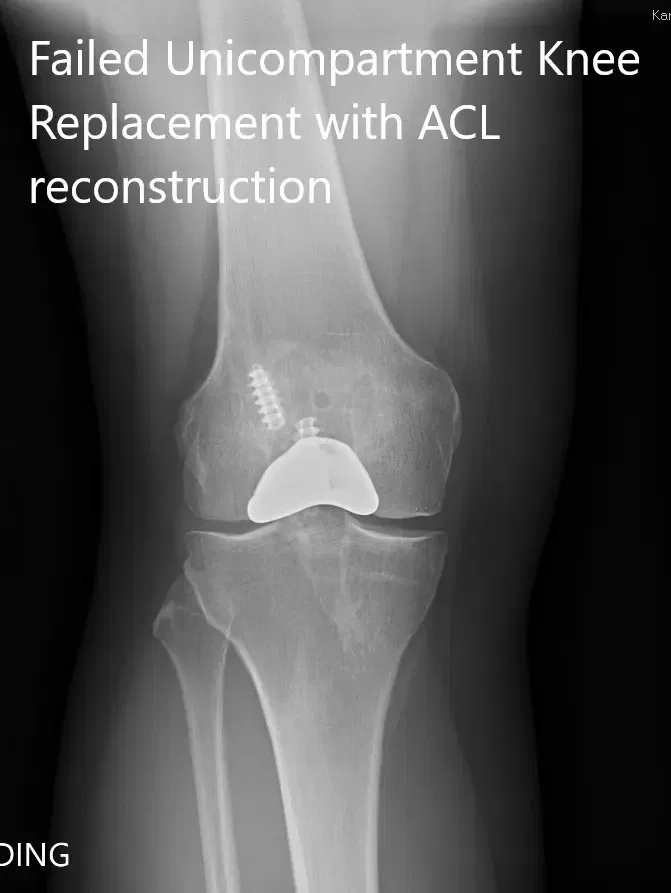

Preoperative x-ray showing the anteroposterior and lateral views of the right knee

The results of his investigations were within normal limits. There was no evidence of infection of the right knee. Imaging revealed failure of the partial knee replacement. He was advised a revision total knee replacement in view of advanced osteoarthritis. He agreed with the plan.

PREOPERATIVE DIAGNOSIS(ES): Failed Right knee unicondylar knee replacement.